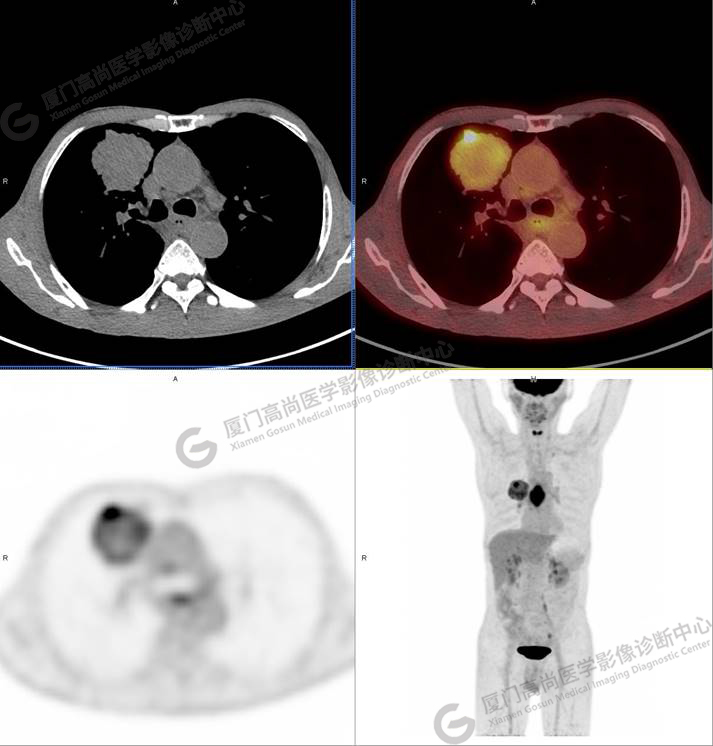

右肺上葉軟組織密度腫塊,大小約5.9×5.5×6.3cm,形態(tài)不規(guī)則,邊緣見棘突,其內(nèi)密度不均勻,放射性攝取不均勻性增高,SUVmax 6.46;腫塊周圍見多發(fā)小結(jié)節(jié)影,較大者直徑約0.6cm,放射性攝取未見明顯增高。影像學(xué)表現(xiàn)考慮右肺癌并肺內(nèi)轉(zhuǎn)移。

同時發(fā)現(xiàn)食管中段管壁增厚,管腔狹窄,放射性攝取不均勻性增高,SUVmax 9.67。

多原發(fā)癌指同一患者體內(nèi)單個或多個器官組織同時或先后發(fā)生兩種或兩種以上的原發(fā)性惡性腫瘤。國內(nèi)外對多原發(fā)癌發(fā)病率的報道有一定差異,隨著PET/CT應(yīng)用的普及,多原發(fā)癌的檢出率有所上升。本例右肺腫塊和食管占位的臨床及影像學(xué)表現(xiàn)都很典型,但咳嗽、咳痰的癥狀更重,進(jìn)食哽噎癥狀被忽視,在患者做PET/CT檢查前臨床未考慮到合并食管癌的可能性。